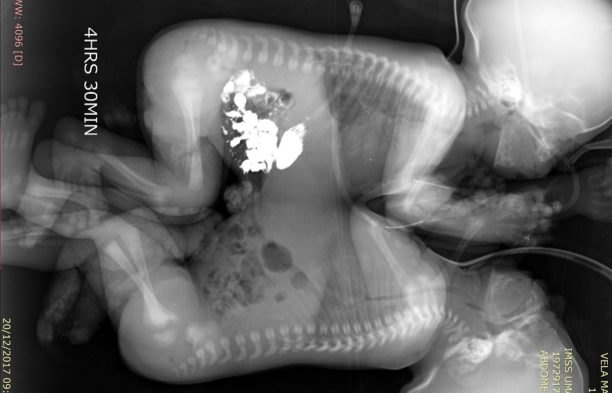

Tras diversos exámenes de tomografía, ecocardiograma y resonancia magnética, cuando los niños cumplieron 41 días de vida, fueron programados para la cirugía que los separaría.

El equipo multidisciplinario de cirujanos, anestesistas y enfermería, dio inicio a la operación a las 9:00 horas; de manera cuidadosa realizaron la incisión en la línea media que unía a los gemelos y mediante la técnica de electrocoagulación, lograron separarlos a las 12:43 horas, sin que se presentaran complicaciones.